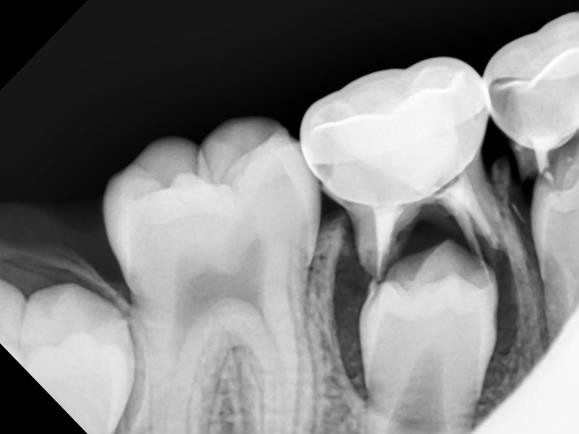

Despite this medication's positive effects, one possible side effect of using bisphosphonate drugs is bisphosphonate-induced osteonecrosis of the jaw (ONJ), which is very similar to phossy jaw. The American College of Rheumatology (ACR) describes ONJ as a condition where the jawbone becomes exposed and doesn't get enough blood, so it begins to weaken and die, often causing pain. An individual who is taking or has previously taken bisphosphonate medication is at a greater risk for ONJ, and it most commonly occurs following dental extractions.

It's common for dental professionals to advise patients who need extractions to discontinue the use of bisphosphonate drugs and take an antibiotic prior to the procedure, explains Johns Hopkins Medicine. This is because, while bisphosphonates are used to prevent bone thinning, they can interfere with jawbone healing, especially after dental work.

Bisphosphonate-induced ONJ is rare, as the National Osteoporosis Foundation notes. But ONJ can also occur in individuals who have not taken bisphosphonate drugs. Other risk factors for ONJ include radiation treatment, infection and steroid use.